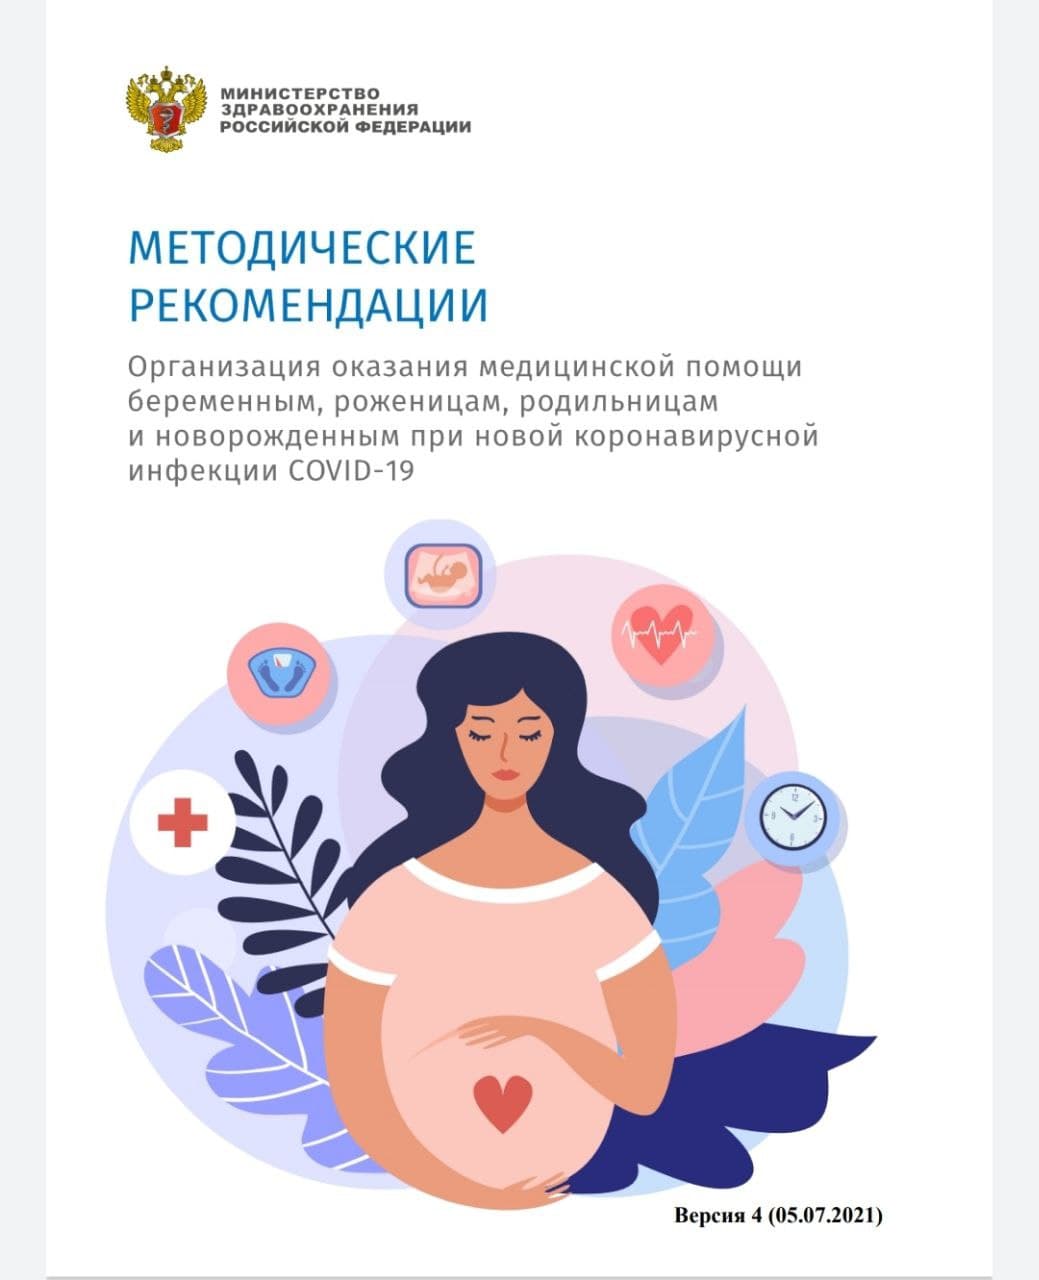

07.07.2021

Выпущена четвёртая версия методрекомендаций по организации медпомощи беременным и новорожденным с COVID-19

Замминистра Марина Бичурина: «Будущим мамам нужно объяснить, почему особенно важно защитить на этом этапе свое здоровье и здоровье своего ребёнка»

Подробнее...

Вакцинация от коронавируса способна защитить здоровье беременной женщины и ее будущего малыша

Подробнее...